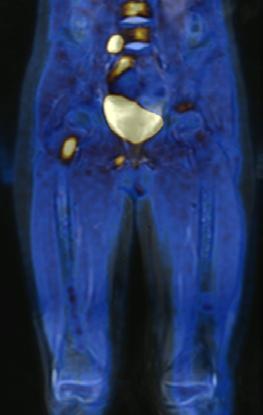

Figura 1A) Estudio PET con 6-[18F]FDOPA positivo para actividad tumoral del primario conocido en abdomen y retroperitoneo, con metástasis difusas en la médula ósea del esqueleto axial y apendicular.

Figura 1B) Estudio PET con [18F]OCTREOTIDE con sobreexpresión anormal de los receptores de somatostatina en retroperitoneo y esqueleto axial y apendicular.

Al correlacionar con 6-[18F]DOPA (Figura 1A) se observa que las lesiones tienen mayor sobreexpresión de los receptores de somatostatina.

Femenino de 7 años con diagnóstico de Neuroblastoma, se realiza PET/RM con [18F]F-DOPA para estadiaje, con evidencia de lesión primaria a nivel de retroperitoneo y conglomerados locoregionales así como infiltración a médula ósea del esqueleto axial y apendicular (Figura 1A), posteriormente la paciente fue tratada quirúrgicamente con resección de la lesión primaria así como tratamiento con inmunoterapia y transplante autólogo de médula ósea además de radioterapia. Al presentar refractariedad al tratamiento comentado, se plantea la posibilidad de administrar Lutecio (177Lu) oxodotreotide, por lo que se sugiere realizar PET/RM con [18F]Octreotide para valorar expresión de receptores de somatostatina y considerar la terapia con radionúclidos para receptores de péptidos (PRRT), el estudio muestra evidencia de sobreexpresión anormal de dichos receptores en retroperitoneo, espacio subpleural izquierdo además de esqueleto axial y apendicular (Figura 1B).

Estudio PET con 6-[18F]DOPA 3A) y [18F]OCTREOTIDE 3B) en cortes coronales de secuencias T2 de miembros pélvicos y con imágenes fusionadas, donde se identifica mayor sobreexpresión anormal de los receptores de somatostatina al compararlos con 6-[18F]DOPA, y que hace candidata a la paciente para PRRT.